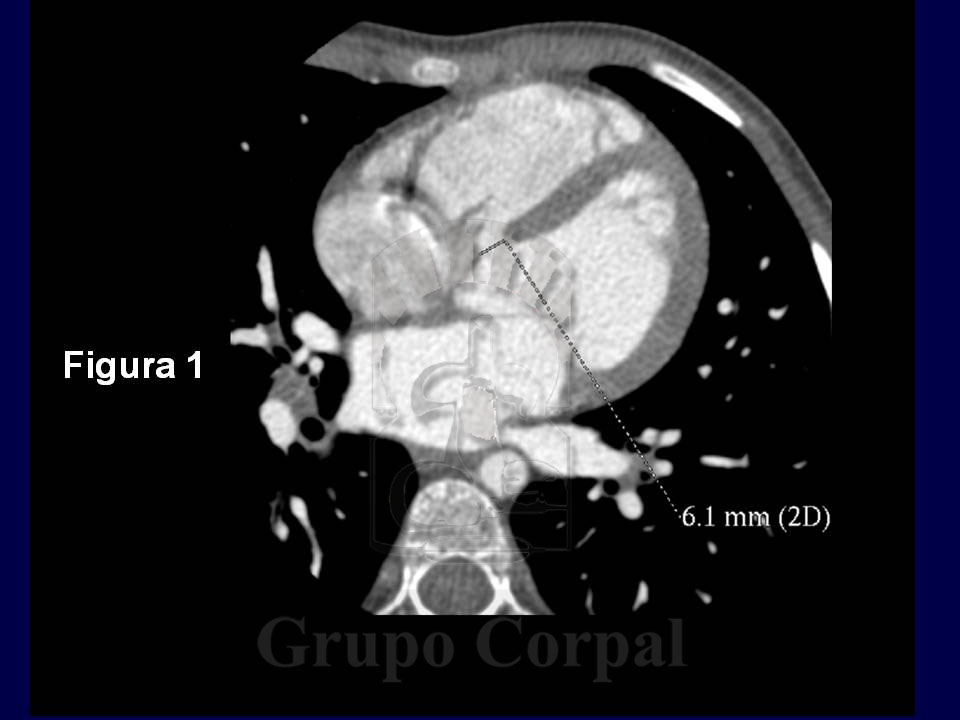

Un joven paciente de 16 años, consultó por habérsele detectado un soplo en un reconocimiento rutinario. Fue diagnosticado de Comunicación Interventricular (CIV) y estudiado por TAC-multicorte (Figura 1). En dicho estudio, puede observarse una CIV subaórtica de 6 mm de diámetro. Se programó para cierre percutáneo mediante cateterismo cardiaco.